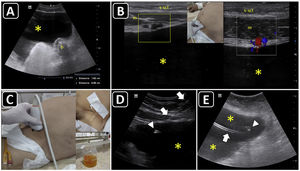

PreprocedureA convex or a phased-array probe is used to assess the view where the effusion accumulation is maximal and closest to the transducer. The thickness of the effusion is measured in diastole in each window, while the distance from the skin to the parietal pericardium and to the myocardium (visceral pericardium) should be obtained to estimate the needle depth of insertion and needle length (Fig. 2A–C). Qualitative assessment should also be performed. While anechoic fluid can be either a transudate or an exudate, the presence of debris or septations points towards the latter. Quantitative and qualitative assessments aid in decision making regarding whether pericardiocentesis, another procedure, or no procedure should be performed. Using a linear probe, the pleura, internal thoracic vessels, and intercostal vessels are delineated to exclude these structures from the needle trajectory (Fig. 2D, E.50

Ultrasound-guided pericardiocentesis. A) Subcostal 4 chamber view. B) Parasternal long-axis view. C) Apical view. As noted, the optimal window to insert the needle is the apical, given the shorter distance to reach the pericardial space (continuous green line) and higher pericardial fluid thickness (continuous yellow line). RA, right atrium; RV, right ventricle; LA, left atrium; LV, left ventricle; RVOT, right ventricular outflow tract. Asterisks indicate pericardial effusion. Adapted from Blanco P, Figueroa L, Menéndez MF, Berrueta B. Pericardiocentesis: ultrasound guidance is essential. Ultrasound J. 2022;14(1):9. https://theultrasoundjournal.springeropen.com/articles/10.1186/s13089-022-00259-5. (CC-BY-4.0). D) Recognition of the left internal thoracic vessels along the left parasternal line (dotted white line) with a linear probe on two-dimensional and color Doppler imaging; s-sct, skin-subcutaneous tissue; m, intercostal muscle; r, rib; arrowhead, pleura; asterisks, internal thoracic vessels. E) Recognition of the intercostal vessels with a linear probe on color Doppler imaging. Real-time in-plane ultrasound-guided pericardiocentesis via intercostal approach (apical view) using a linear probe. The needle (arrows) is entirely observed in the pericardial space (asterisks); LV: left ventricle. G) Hemorrhagic fluid is freely evacuated from the pericardial space after catheter placement.

There are two broad approaches to perform ultrasound-guided pericardiocentesis, which is a real-time procedure: intercostal (apical and left parasternal) and subcostal. The former is the preferred route, given that there is often a shorter distance for the needle to reach the pericardial cavity compared with the subcostal approach. However, it largely depends on the site of maximal fluid accumulation, which is usually non-uniform.49

A phased-array probe or convex probe is chosen to guide the procedure. Wherever possible, a linear probe aids in the best observation of the needle, particularly in intercostal pericardiocentesis (Fig. 2F). The entire intervention is performed under full sterile barrier precautions.

Pericardiocentesis is performed using a specific kit, or, eventually, in austere settings, a central venous cannulation kit.

After disinfecting and infiltrating the target site with local anesthetics, the needle is inserted in-plane into the pericardial cavity; after aspiration a few milliliters of pericardial fluid, 5 ml of agitated saline are injected through the needle. The immediate appearance of echo contrast in the pericardial space confirms that the needle is in the pericardial cavity and rules out a cardiac chamber perforation51(Video 3). The guidewire is then passed and observed in the pericardial space, and, after dilation, the catheter is finally accommodated (Fig. 2G) and connected to a three-way stopcock and a drainage system.

PosprocedureRechecking lung sliding is mandatory when using an intercostal approach. If catheter drainage function is optimal, serial ultrasound assessments will show a reduction in the amount of pericardial fluid. When using the subcostal approach, the liver should be observed for a hematoma, and the presence of free peritoneal fluid should also be assessed.